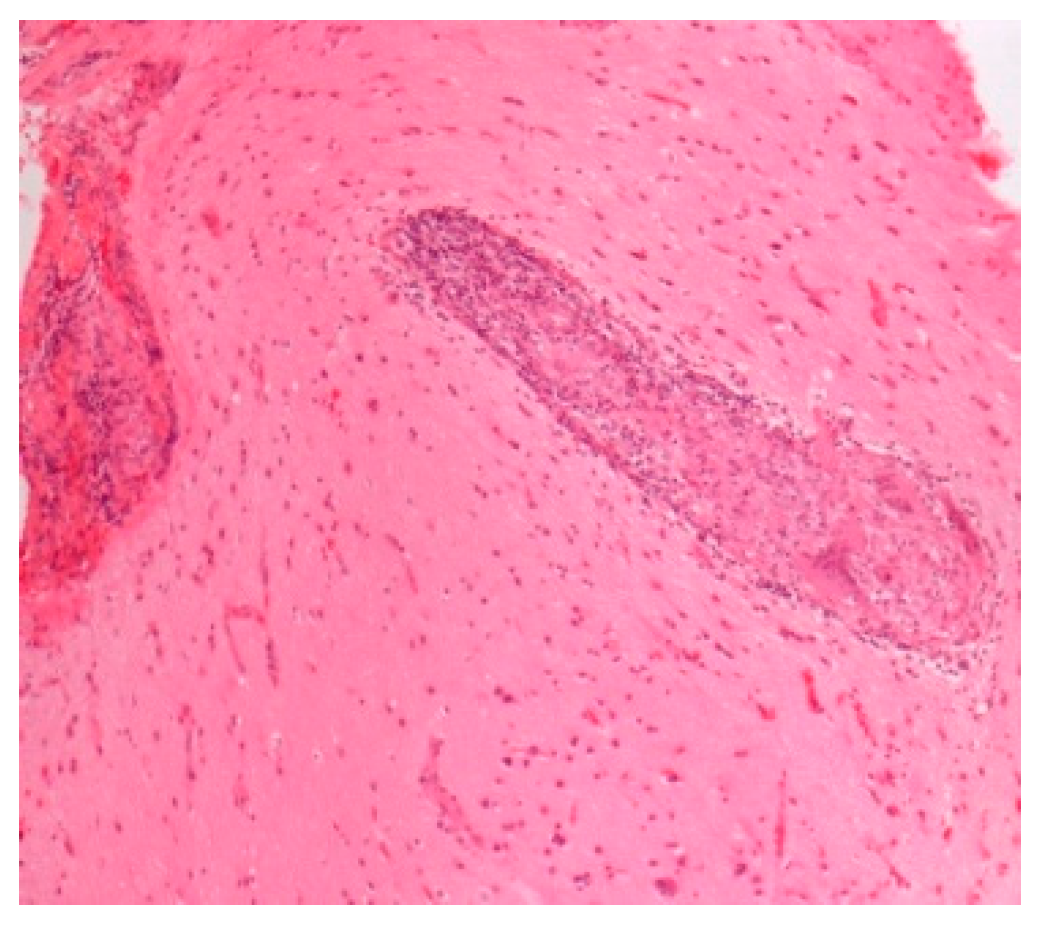

| -Prevalence -Systems involved -Prognosis | -0.22–0.29/106 -Lymph nodes/Lung -Chronic disease 12% | BAL: CD4/CD8 Biopsies | Granulomas Figure 1 | [2,8,11,13,15] |